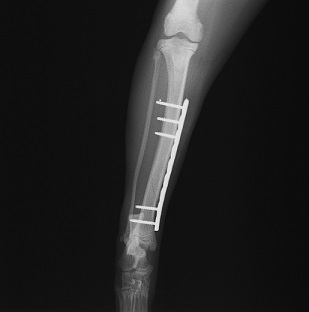

手術前 手術後

ロッキングプレートで整復しました。